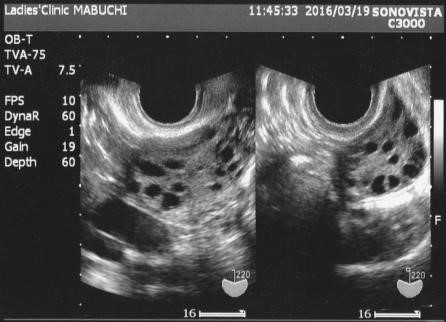

③ 다낭성 난소

초음파에서 난소에 지름 2~9mm의 난포가 12개 이상 관찰되거나, 난소의 크기가 10ml 이상인 경우

기초 혈액검사(호르몬, 혈당, 인슐린 수치 등)와 함께 복부 또는 질식 초음파 검사를 병행합니다.